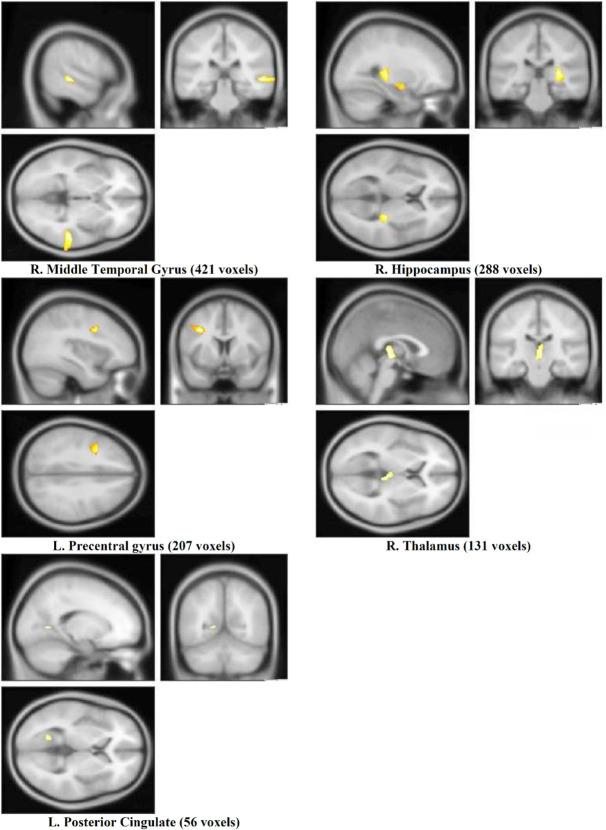

The obtained data presented a larger volume in a total number of 1103 voxels of the brain (in 5 brain areas) in the military group. Furthermore, the military group suggested higher brain activation in the visual processing areas of the brain when observing real combat videos; however, this increment was mostly in the areas associated with motor processing and executive functions in the controls.

所获得的数据显示,军人组大脑中总共1103个体素(分布在5个脑区)的体积更大。此外,军人组在观看真实战斗视频时,大脑视觉处理区域的激活程度更高;然而,对照组的这种增加主要出现在与运动处理和执行功能相关的区域。